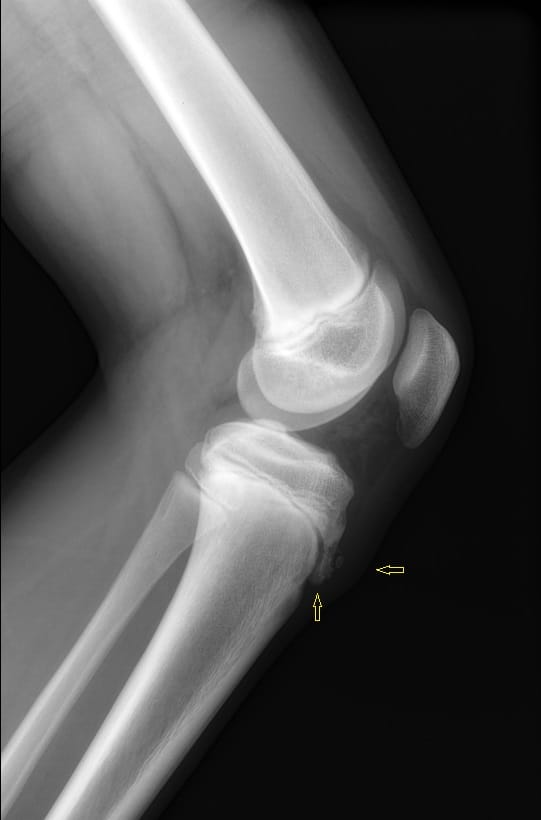

Viêm lồi củ trước xương chày

Viêm lồi củ trước xương chày - Ảnh 3

» Thông tin: Nam giới – 10 tuổi.

» Lâm sàng: Sưng đau đầu trên xương chày.